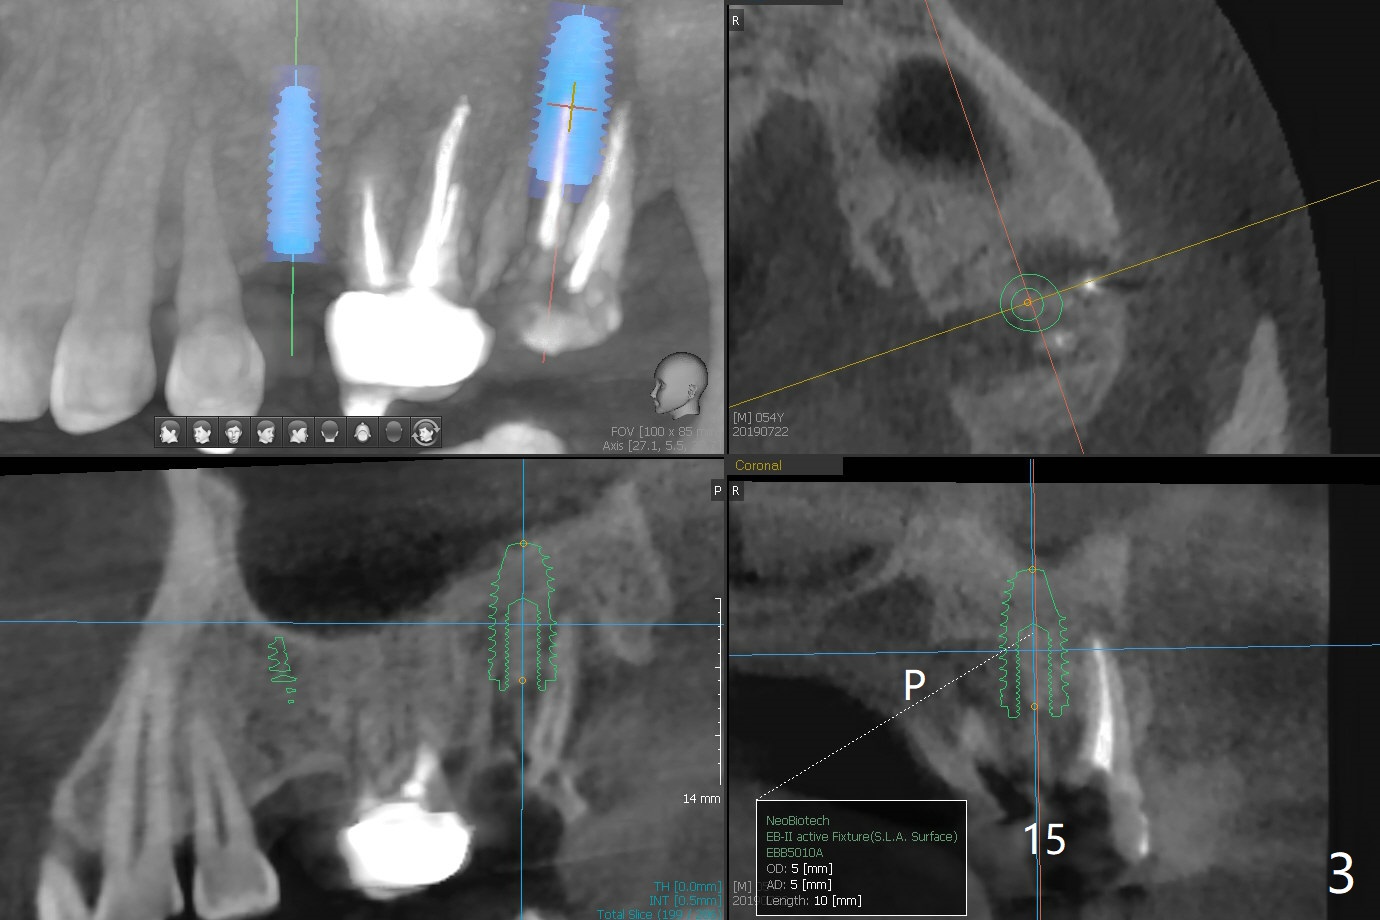

A 54-year-old man has lost a crown at #15 due to root fracture. The latter is associated with bruxism and missing #13. He agrees to have 2 implants and limited ortho to increase the space at #13. In fact the space increases by proximal reduction before CT and impression for guide (Fig.1). The space is enough for a narrow metal sleeve (Fig.4). To prove that abutment screw loosening is most likely related to implant trajectory, IBS implants (with history of easy screw loosening) will be placed with the help of IS guide. PRF will be prepared (x2), one for sinus lift and the other for palatal plate repair. Take photos for palatal fistula.